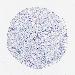

UROTHELIAL CANCER - Protein expressioni

A mouse-over function shows sample information and annotation data. Click on an image to view it in a full screen mode. Samples can be filtered based on level of antibody staining by selecting one or several of the following categories: high, medium, low and not detected. The assay and annotation is described here.

Note that samples used for immunohistochemistry by the Human Protein Atlas do not correspond to samples in the TCGA dataset.

Antibody stainingi

Antibody staining in the annotated cell types in the current human tissue is reported as not detected, low, medium, or high, based on conventional immunohistochemistry profiling in selected tissues. This score is based on the combination of the staining intensity and fraction of stained cells.

Each image is clickable and will lead to virtual microscopy that enables deeper exploration of all samples and also displays staining intensity scores, fraction scores and subcellular localization as well as patient and tissue information for each sample.

Antibody HPA003074

Staining

High

Medium

Low

Not detected

Intensity

Strong

Moderate

Weak

Negative

Quantity

>75%

75%-25%

<25%

None

Location

Nuclear

Cytoplasmic/membranous

Cytoplasmic/membranous,nuclear

Urothelial carcinoma, High grade